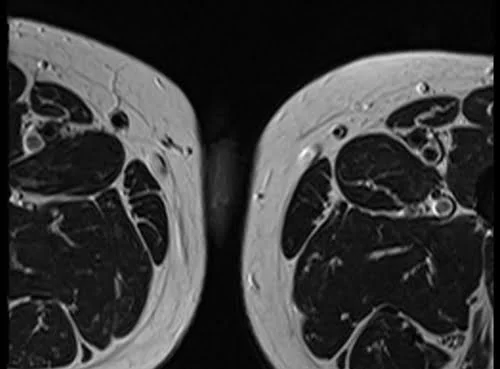

MRI testis sfov axial t2 high res image 2 - MRI